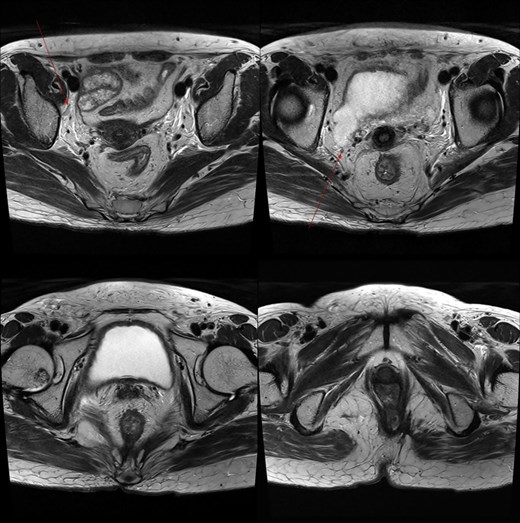

A 59-year-old female patient was referred to our hospital with severe left buttock pain lasting 5 days. Although she had no co-morbidities, she was previously diagnosed with hemorrhoids at the local clinic due to perianal pain persisting for 1 month. The patient had no medical or surgical history. Her initial body temperature was 38.4°C, blood pressure was 110/60 mmHg, heart rate was 98 beats/min, and her oxygen saturation was 98% on room air. On physical examination, erythema and hardness were noted in the left perineum and buttock areas. Additionally, dilated piles were observed on anus (Fig. 1). Given the clinical suspicion of FG, a computed tomography (CT) scan and blood tests were urgently performed. The CT scan demonstrated abscess formation along with severe emphysema in the left perineum and buttock (Fig. 2A). Blood tests showed leukocytosis of 41 840/μl with neutrophil left shift and an elevated C-reactive protein level of 33.4 ng/dl. The patient was finally diagnosed with FG, indicated by a severity index score of 6 points [6]. After initiating fluid resuscitation and broad-spectrum antibiotics, extensive debridement of the perineum was executed (Fig. 2B). However, due to clinical deterioration after general anesthesia, staged debridement was performed, and the patient was admitted to the intensive care unit for stabilization. Subsequent debridement and a diverting colostomy were performed 3 days after surgery. After 1 week in intensive care, the patient was transferred to the general ward where additional wound debridement and revisions were conducted. Two months after initial surgery, the surgical wound had completely healed, and wound closure was performed. Although inflammation had subsided, indurated tissue persisted around the anus, which had become so constricted that a digital rectal examination was impeded. Therefore, a biopsy of the perianal tissue was taken. Histopathological examination identified moderately differentiated squamous cell carcinoma, and HPV 16 was detected (Fig. 3). Pelvic magnetic resonance imaging (MRI) revealed anorectal cancer with invasion into both levator muscles and indeterminate lymph nodes in the bilateral external iliac, right obturator, and bilateral inguinal chains (Fig. 4). Positron emission tomography demonstrated an intensely hypermetabolic mass extending from the anus to the rectum, accompanied by multiple hypermetabolic lymph nodes in the left common iliac, left external iliac, right internal iliac, and bilateral inguinal regions (Fig. 5). Consequently, concurrent chemoradiotherapy (CCRT) employing mitomycin and 5-fluorouracil was initiated. The patient received a total radiation dose of 63 Gy in 35 fractions over 8 weeks. Elective nodal irradiation included the bilateral inguinal, internal iliac, and mesorectal nodal basins, in accordance with standard guidelines. Although follow-up MRI after CCRT showed a significant reduction in the size of the primary tumor and lymph nodes, we decided to perform a radical resection (Fig. 6). Robotic abdominoperineal resection was performed 3 months after CCRT, during which lateral pelvic lymph node dissection wasn’t conducted, as post CCRT imaging showed indeterminate lymph nodes suggestive of remission. Histopathological examination of the specimen revealed no residual tumor (ypT0N0). Although a minor surgical site infection occurred at the perineal wound, it was successfully treated with oral antibiotics and dressings at an outpatient setting. At 10 months post-surgery, the patient reported left pelvic pain, and follow-up imaging revealed suspected metastases in the left psoas, para-aortic area, supraclavicular node, right 10th rib, and lung. Consequently, the patient was scheduled for palliative chemotherapy.

Marked reduction in the size of the tumor and lymph nodes following CCRT.